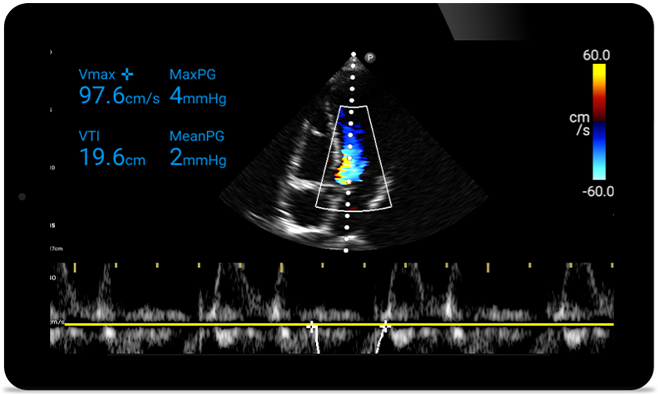

Lumify S4-1 broadband phased array transducer

• 4 to1 MHz extended operating frequency range.

• 2D, Color Doppler, M-mode, advanced, XRES and multivariate harmonic imaging.

• High-resolution imaging for abdominal and cardiac applications: cardiac, OB/GYN, lung, abdomen and FAST imaging preset optimizations.